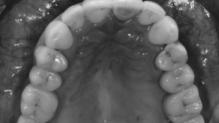

Damit ein Implantat langfristig erfolgreich ist, müssen einige Bedingungen erfüllt sein: